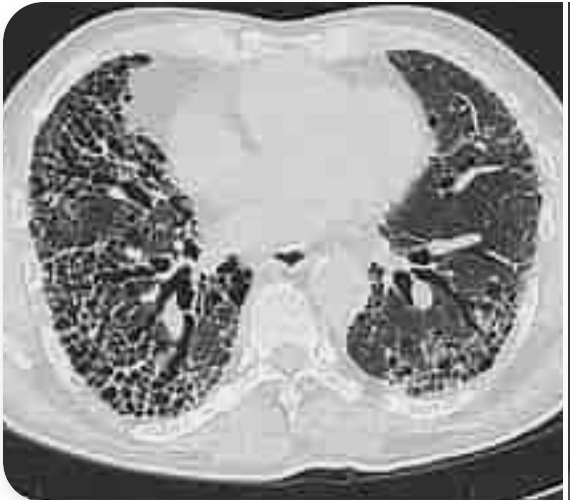

HRCT findings in inflammatory myopathy ILD

A

Patchy consolidation

reticular pattern

UIP/NSIP/COP